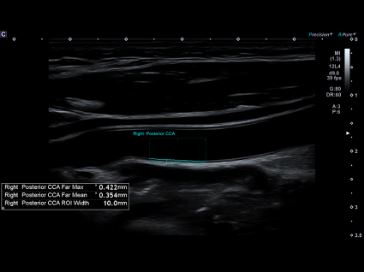

Автоматичне вимірювання комплексу інтима-медіа  Auto IMT допомагає підвищити як точність, так і швидкість допплерівських досліджень сонної артерії.